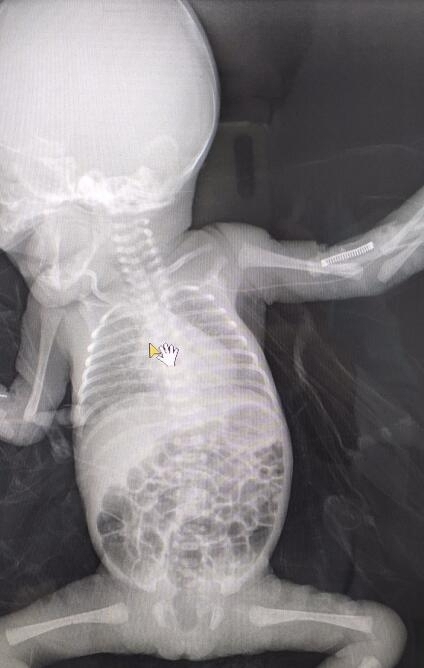

4月7日,区人民医院静疗小组成功为一例体重0.9kg早产儿行PICC置管术,开启了医院早产儿静脉营养输液通道的新纪元。

近日,区人民医院新生儿重症监护室收治了一位体重仅0.9kg的早产新生儿。由于低体重新生儿各项生理机能未发育完善,在出生早期所需营养主要来自静脉营养,而患儿皮肤娇嫩,血管又细,给静脉穿刺带来极大困难,加之其周围小静脉血管壁很薄,高浓度的营养液给患儿刺激太大,极易出现静脉炎、外渗,严重者可造成局部坏死等不良反应,还会增加患儿痛苦及感染几率。为使患儿得到安全、有效的治疗,经静疗小组会诊后,决定为患儿行PICC置管。但我院尚未对如此低体重早产儿实施过PICC穿刺技术,难度可想而知。救人要紧,肿瘤科护士长、静疗小组组长王静、儿二科护士长辛萍凭借先进的技术及丰富的临床经验精准操作,最终成功为患儿实施PICC中心静脉置管术,及时为患儿开辟了一条挽救生命的绿色通道。

使用PICC导管可为患儿提供中期至长期的静脉输液治疗(7天至1年),大大降低药物对血管的损伤,减少静脉炎发生率,避免因周围静脉输注可能导致局部皮肤损伤甚至坏死的发生,最大程度保护患儿脆弱的外周静脉。此次新生儿PICC置管技术的成功实施系医院首例,填补了医院低体重早产儿PICC置管技术的空白。